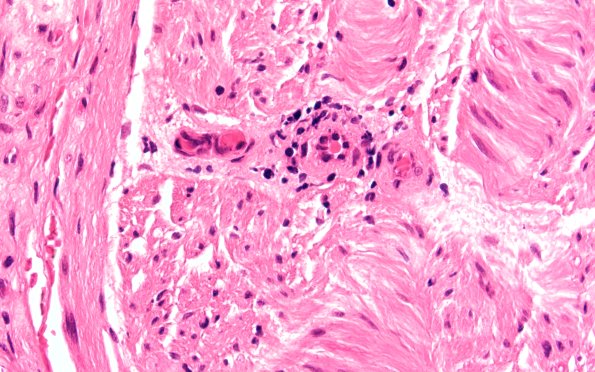

Washington University Experience | PERIPHERAL NEUROPATHY | 9B PERINEURITIS & PERINEURIAL PATHOLOGY | 4A6 Perineuritis (Case 4) H&E 60X 1

Endoneurial inflammation is always abnormal and should be investigated since the differential diagnosis includes a paraneoplastic process. (H&E) ---- Not shown: An AFB stain shows no evidence of acid fast bacilli. A trichrome stain shows no evidence of amyloid deposition. An immunohistochemical stain for CD45 highlights the inflammatory cells. The stain for collagen type IV shows abundant Schwann cell-associated, perivascular and perineurial basement membrane with prominent thickening/reduplication in affected regions of perineurium. Plastic sections show marked loss of large and small myelinated fibers and inflammation. The morphological, cytochemical, and immunohistochemical features are those of an inflammatory neuropathy with prominent perineuritis.